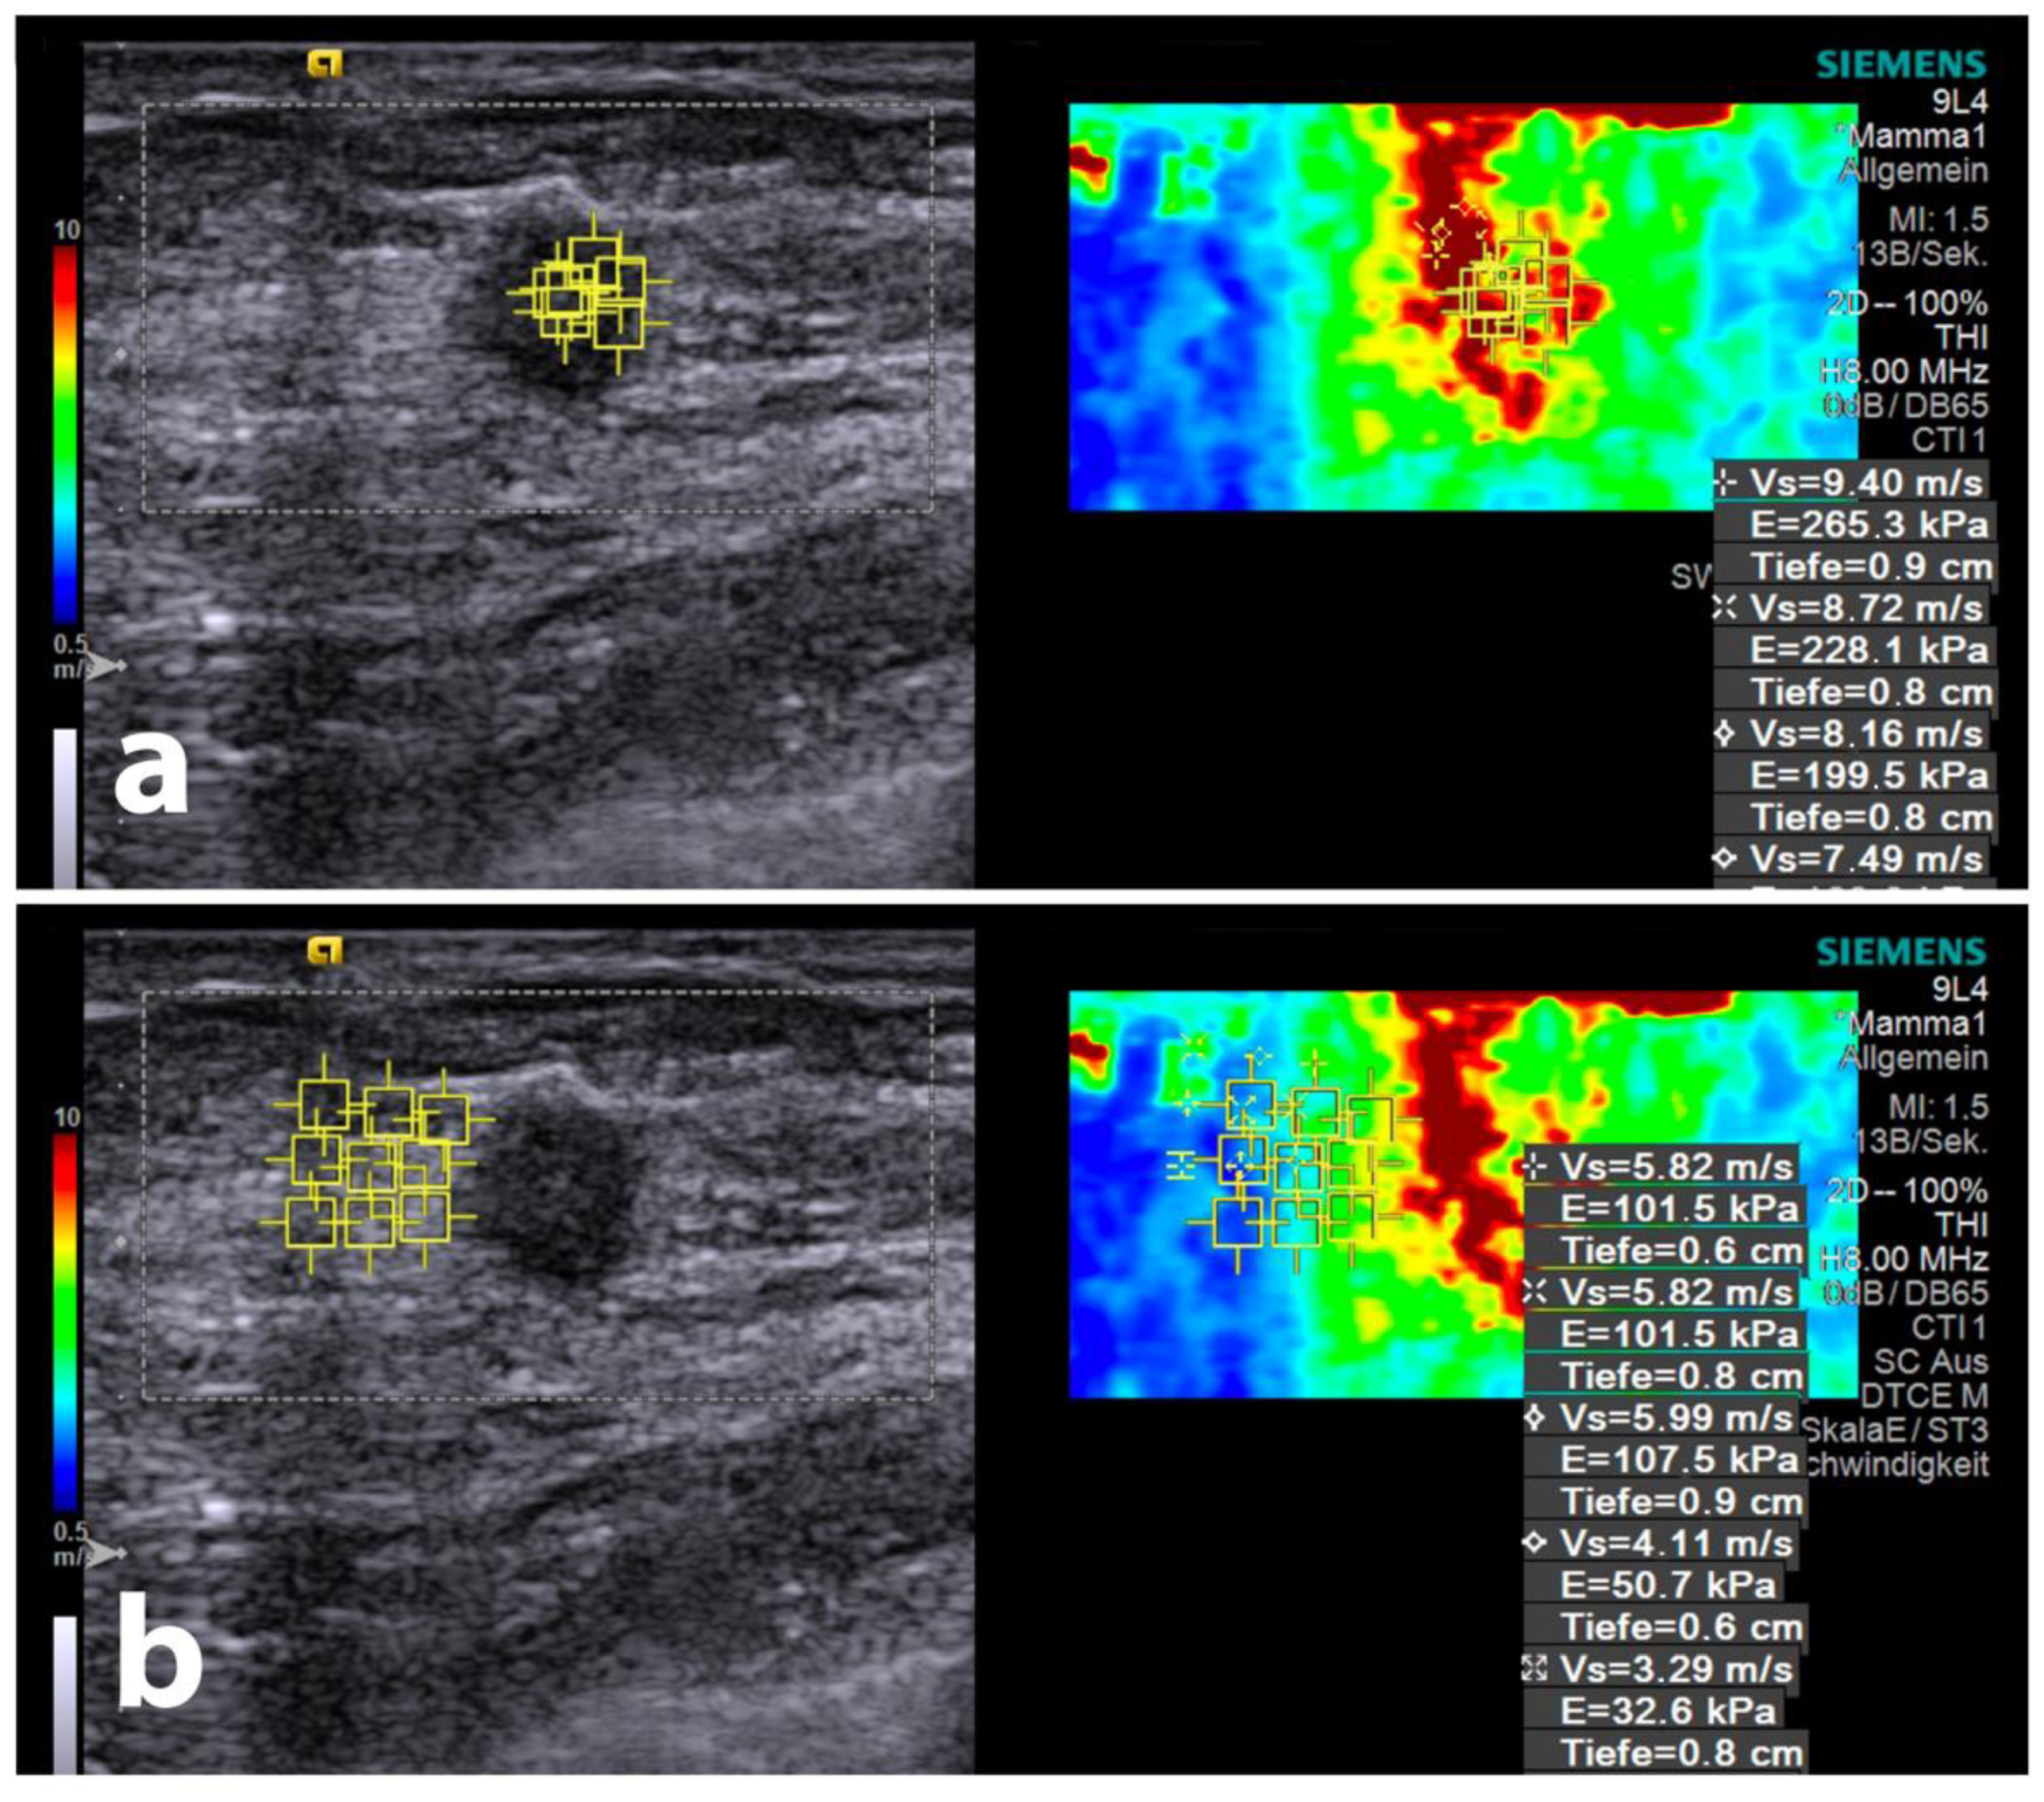

2.3. Ultrasound Equipment, Shear-Wave Elastography Measurements, and Gradient Calculations

3.2. SWE Velocities

3.3. Gradient Analysis